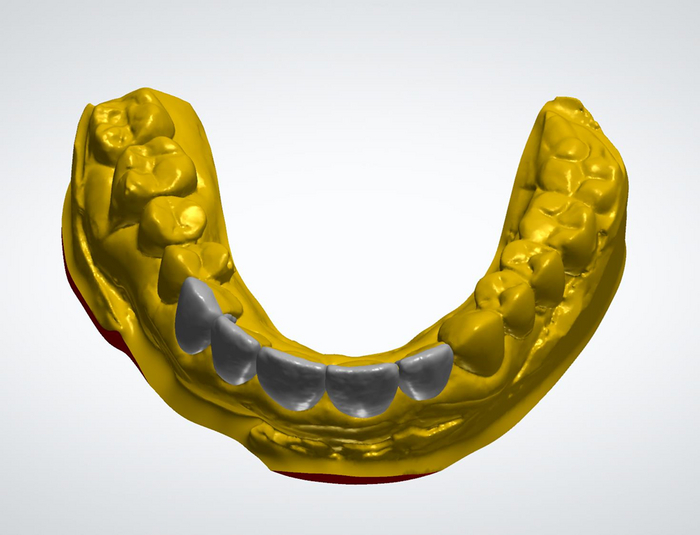

Сага о стоматологии. Глава 42. Для чего стоматологу нужен 3D-принтер?

Для ЛЛ: печатать различные изделия

На этот раз я расскажу про 3D-принтер- одну интересную вундервафлю, которая здорово упрощает мне жизнь.

Рассмотрим простейший пример- изготовление воксапа, то есть моделирование будущего зуба из воска на гипсовой модели. Он применяется при изготовлении капы из Главы 34, а также временных коронок и виниров.

Сперва процесс достаточно похожий. Слепок, гипсовая модель… а вот дальше уходим уже в «цифру», методом 3D-сканирования, то есть переноса данных о поверхности гипсовой модели в виртуальное пространство.

Вернемся к нашим баранам. Допустим, у нас есть цифровая модель ( или слепок, который мы одним кликом мыши в эту модель превращает. Мы кидаем её в специальную софтину в зависимости от задачи и делаем то, что нам надо, либо отправляем зубному технику, который как раз на этом этапе специализируется. Продукт этой работы лежит у нас на компе в виде файла, который нам и надо будет превратить в реальный объект либо с помощью 3D-печати, либо фрезеровки на специальном станке ЧПУ.

Вот скрин 3D-визуализации цифрового воксапа. Чтобы распечатать на 3D-принтере нужно для начала его подготовить к этому делу в другой софтине, которая называется слайсер, то есть нарезает эту модель на мелкие слои, которые наш принтер и будет пропечатывать.